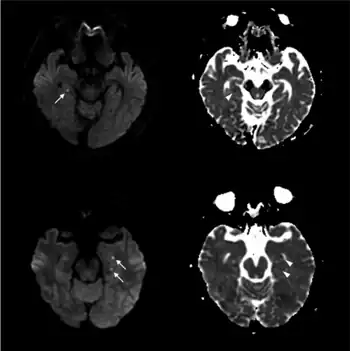

.png.webp)

Unless there are concerning features, limited testing is required.[1] Medical imaging and lumbar puncture are generally not required.[1]

Recently, moreover, both imaging and neurocognitive testing studies question whether TGA is as benign as has been thought. MRI scans of the brain in one study showed that among people who had experienced TGA, all had cavities in the hippocampus, and these cavities were far more numerous, larger, and more suggestive of pathological damage than in either healthy controls or a large control group of people with tumor or stroke.[15] Verbal and cognitive impairments have been observed days after TGA attacks, of such severity that the researchers estimated the effects would be unlikely to resolve within a short time frame.[16] A large neurocognitive study of patients more than a year after their attack has shown persistent effects consistent with amnestic mild cognitive impairment (MCI-a) in a third of the people who had experienced TGA.[37] In another study, "selective cognitive dysfunctions after the clinical recovery" were observed, suggesting a prefrontal impairment.[13] These dysfunctions may not be in memory per se but in retrieval, in which speed of access is part of the problem among people who have had TGA and experience ongoing memory problems.[12]